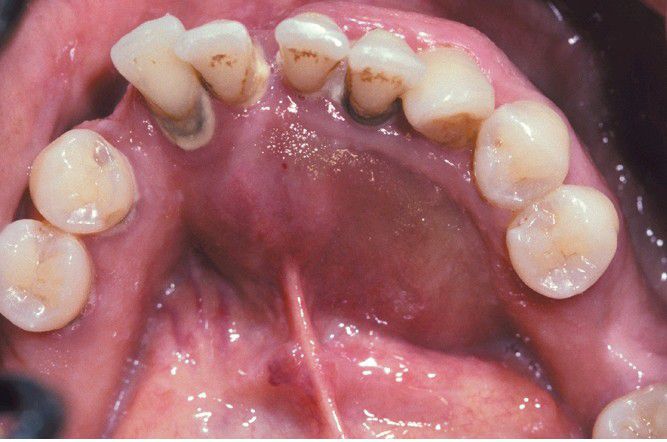

Ameloblastoma

. Prominent expansion of the lingual alveolus caused by a large ameloblastoma of the mandibular symphysis.